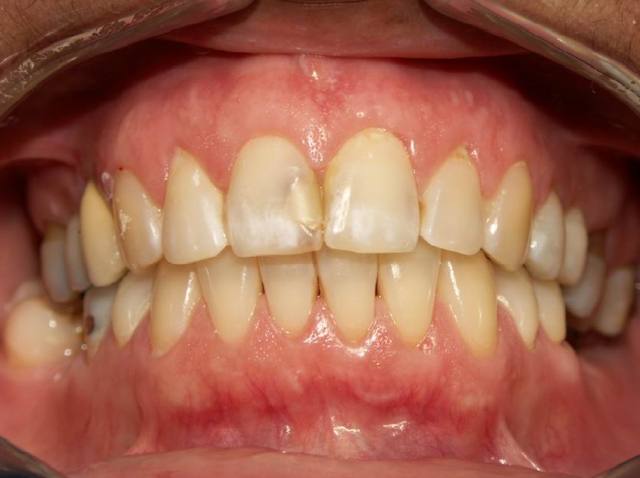

Si vous permettez je commence ça tombe bien je voulais poster ce cas dans les cas cliniques, mais vu que le problème est surtout occluso. Voilà

Patient 45 ans bruxisme, douleurs masseters.

Les points noirs sont les contacts en PIM.

To pote de 45 berges a une déglutition salivaire atypique (= déglutition infantile chez l'adulte) et tu peux certainement "Augmenter sa DVO" (Voir ce titre dans ce même Forum).

C'est exact Jeudi il a vu l'ortho, qui a confirmé une interposition linguale à la déglutition. Un traitement est prévu pour ça pour bientôt et des élastiques pour remonter les PM mdb si le repositionnement correct de la langue ne l'a pas fait.

Si jamais éventuellement par hasard (et ça n'engage à rien) tu voulais vérifier la symétrie de son état de contraction musculaire, fais attention: articulé croisé à gauche, les appuis et les guides ne sont plus à la même place.